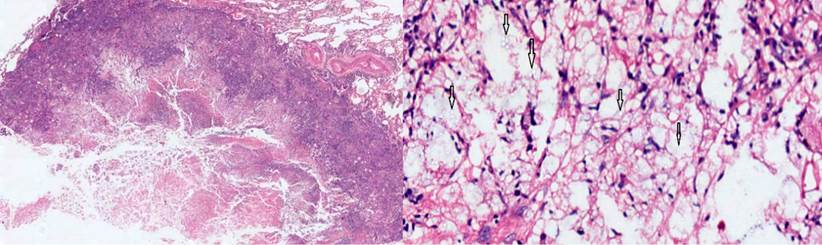

Ante la sospecha de un tuberculoma, se realizó una biopsia en cuña del nódulo del lóbulo inferior, con una patología que reportó un parénquima pulmonar con enfermedad granulomatosa crónica caseificante, compatible con criptococosis, y negativo para bacilos acidorresistentes (BAAR) (Figura 3). Los cultivos de hongos confirmaron un moderado crecimiento de Cryptococcus neoformans, mientras que la PPD negativa descartó la tuberculosis latente.

Figura 3 Con coloración de hematoxilina-eosina, se observa el parénquima pulmonar con un granuloma necrotizante, con detritos e histiocitos. A mayor aumento (10 X), se aprecian en detalle las esporas del criptococo, señaladas con flechas. Fuente: archivo de los autores.

Los medios diagnósticos considerados más específicos son el cultivo y la biopsia del tejido; esta última es la más importante y se puede obtener por punción o quirúrgicamente. Las coloraciones empleadas son las de tinta china, Gomory, ácido peryódico de Schiff (Periodic Acid-Schiff, PAS) y mucicarmina 12. En el caso de nuestro paciente, se realizaron cultivo y biopsia, que demostraron la presencia de las esporas del criptococo.